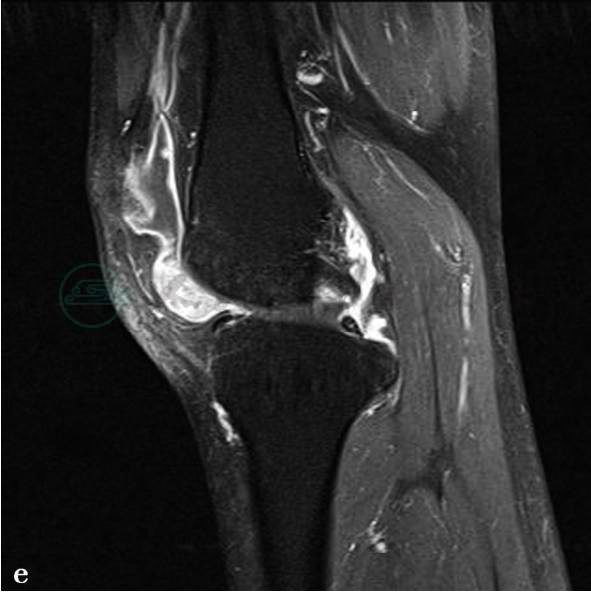

图1 图1a~c,MRI平扫示左膝关节前方髌下关节囊内可见一类圆形占位病变,病灶边缘较清楚,大小约2.3cm× 1.5cm。图1a,病灶在T1WI上呈低信号。图1b,在T2WI脂肪抑制像上呈稍高信号,边界清楚。关节囊内有较多液体信号影,并包绕上述占位病变。内、外侧半月板无异常。前、后交叉韧带连续。髌前软组织内可见高信号。图1d、e,MRI增强扫描示左膝关节前方髌下关节囊内类圆形占位病变明显强化,但信号不均匀。关节囊滑膜弥漫性增厚